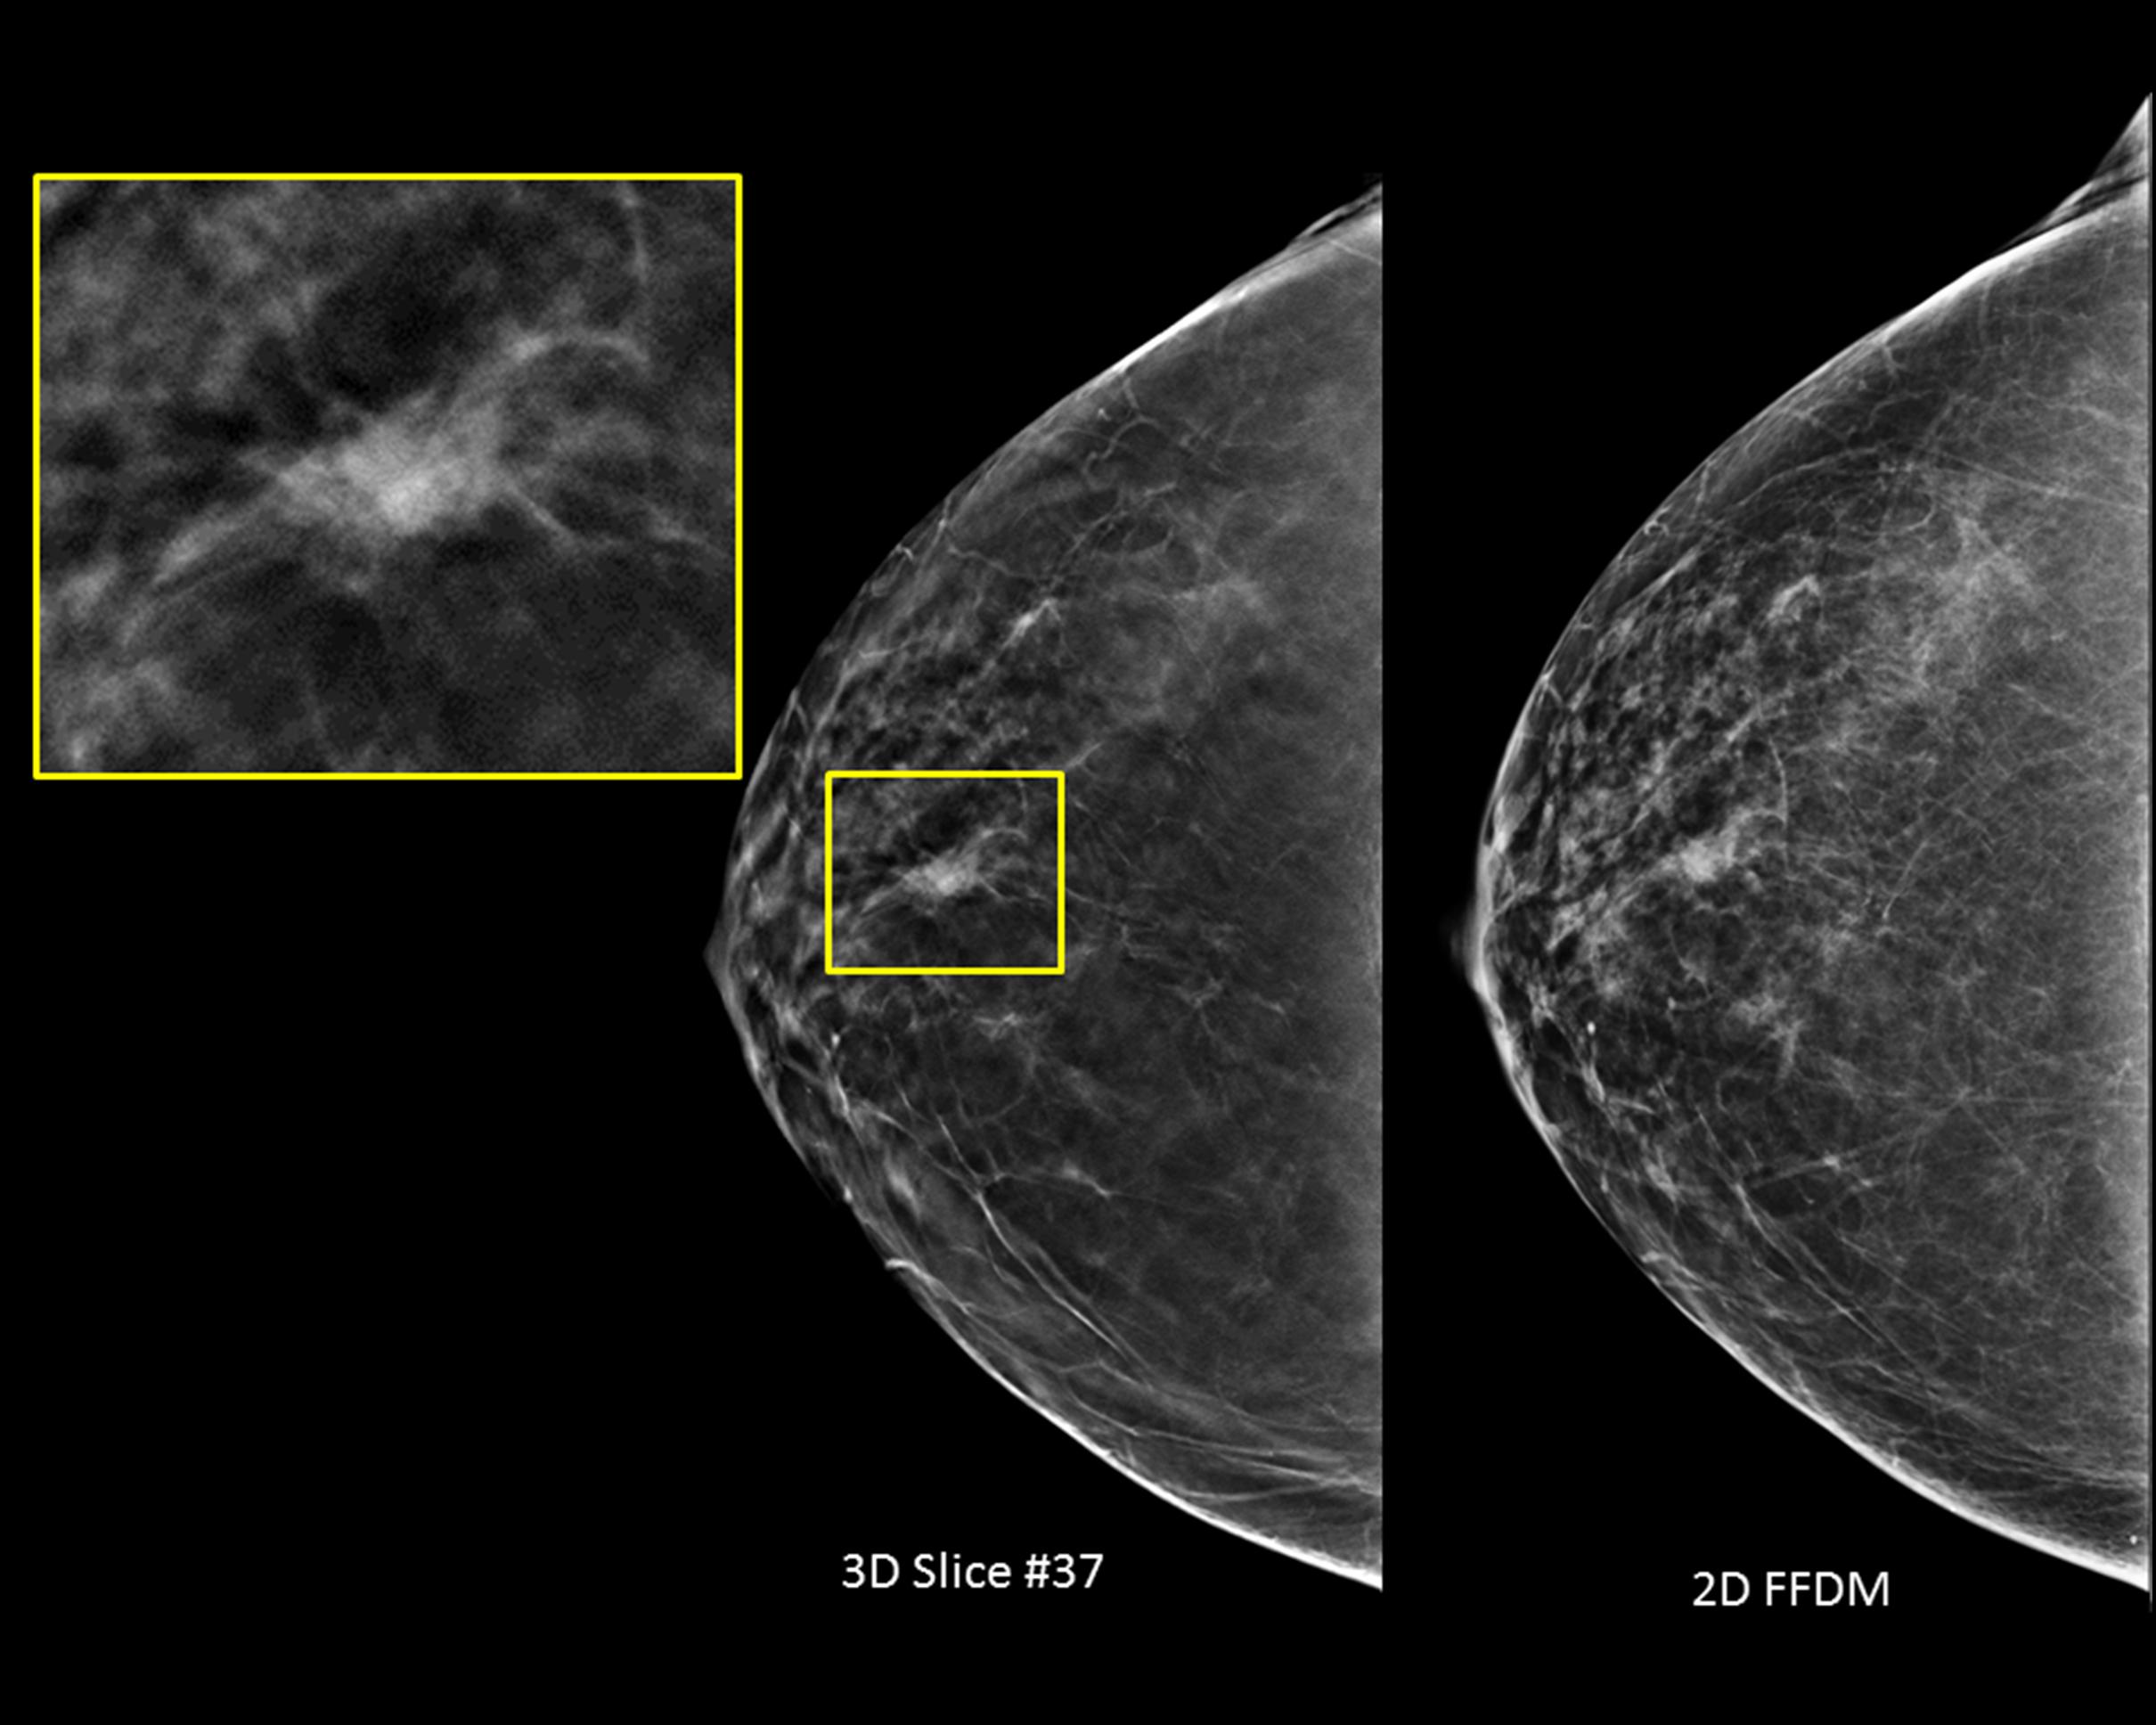

The new 3Dimensions system is designed to provide higher quality 3D images for radiologists, a more comfortable mammography experience for patients and enhanced workflow for technologists. Discover how sharper images and smarter technologies continue to help find invasive cancers regardless of age or breast density.1-6

Designed to be the fastest, highest resolution breast tomosynthesis system, ever.

The new 3Dimensions mammography system matches the unrivaled performance of our Genius 3D Mammography™ exam, which is more accurate than conventional 2D mammograms, detecting 20%-65% more invasive breast cancers.1-8 Breakthrough improvements transform the patient experience without compromising speed or accuracy.

Better visibility

Designed to improve visibility of fine details for greater diagnostic confidence.*